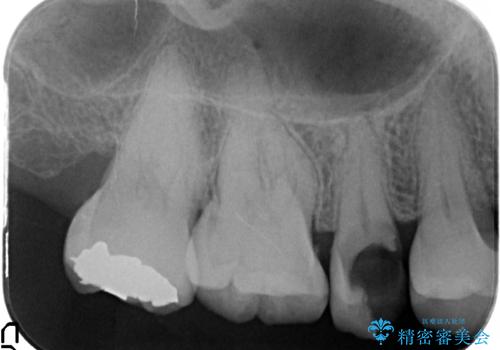

- 大きく歯が欠けてしまった虫歯の治療を希望され来院されました。

虫歯による歯の崩壊で歯を残すことが難しかったので抜歯を行い、インプラント・入れ歯ではなくブリッジによる咬合機能の回復を希望されました。